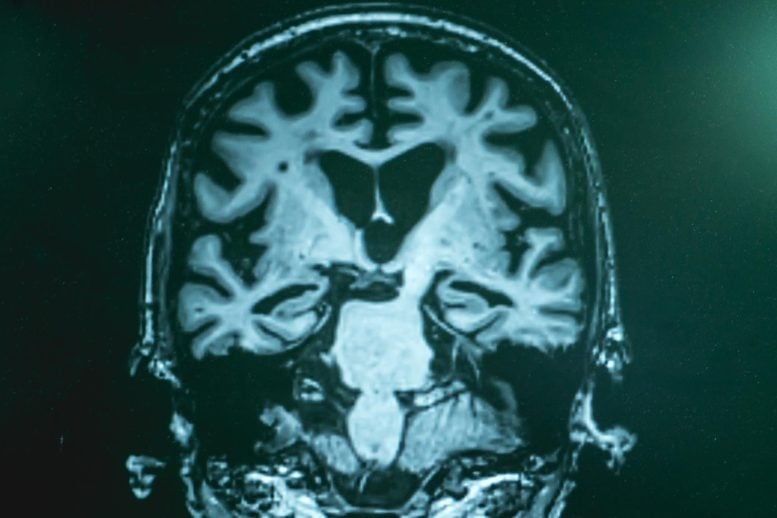

A groundbreaking new imaging technique is shining an unprecedented light on the molecular landscape of Alzheimer’s disease, offering researchers a brain-wide “chemical map” that could transform how we understand, diagnose, and ultimately treat this devastating neurodegenerative condition.

In a landmark study, scientists at Rice University have unveiled what they describe as the first comprehensive, label-free molecular atlas of an Alzheimer’s-affected brain in an animal model. This pioneering work moves far beyond the traditional focus on amyloid plaques—those infamous protein clumps long considered the hallmark of Alzheimer’s—and instead captures a broader, more intricate chemical portrait of the disease.

By using SRH, the Rice team was able to generate a detailed, three-dimensional chemical map of the entire mouse brain affected by Alzheimer’s. This map reveals not just the location of amyloid plaques, but also the distribution of lipids, proteins, and other biomolecules that play crucial roles in brain health and disease. In essence, it provides a panoramic view of the molecular chaos that underlies Alzheimer’s, highlighting disruptions that were previously invisible to researchers.